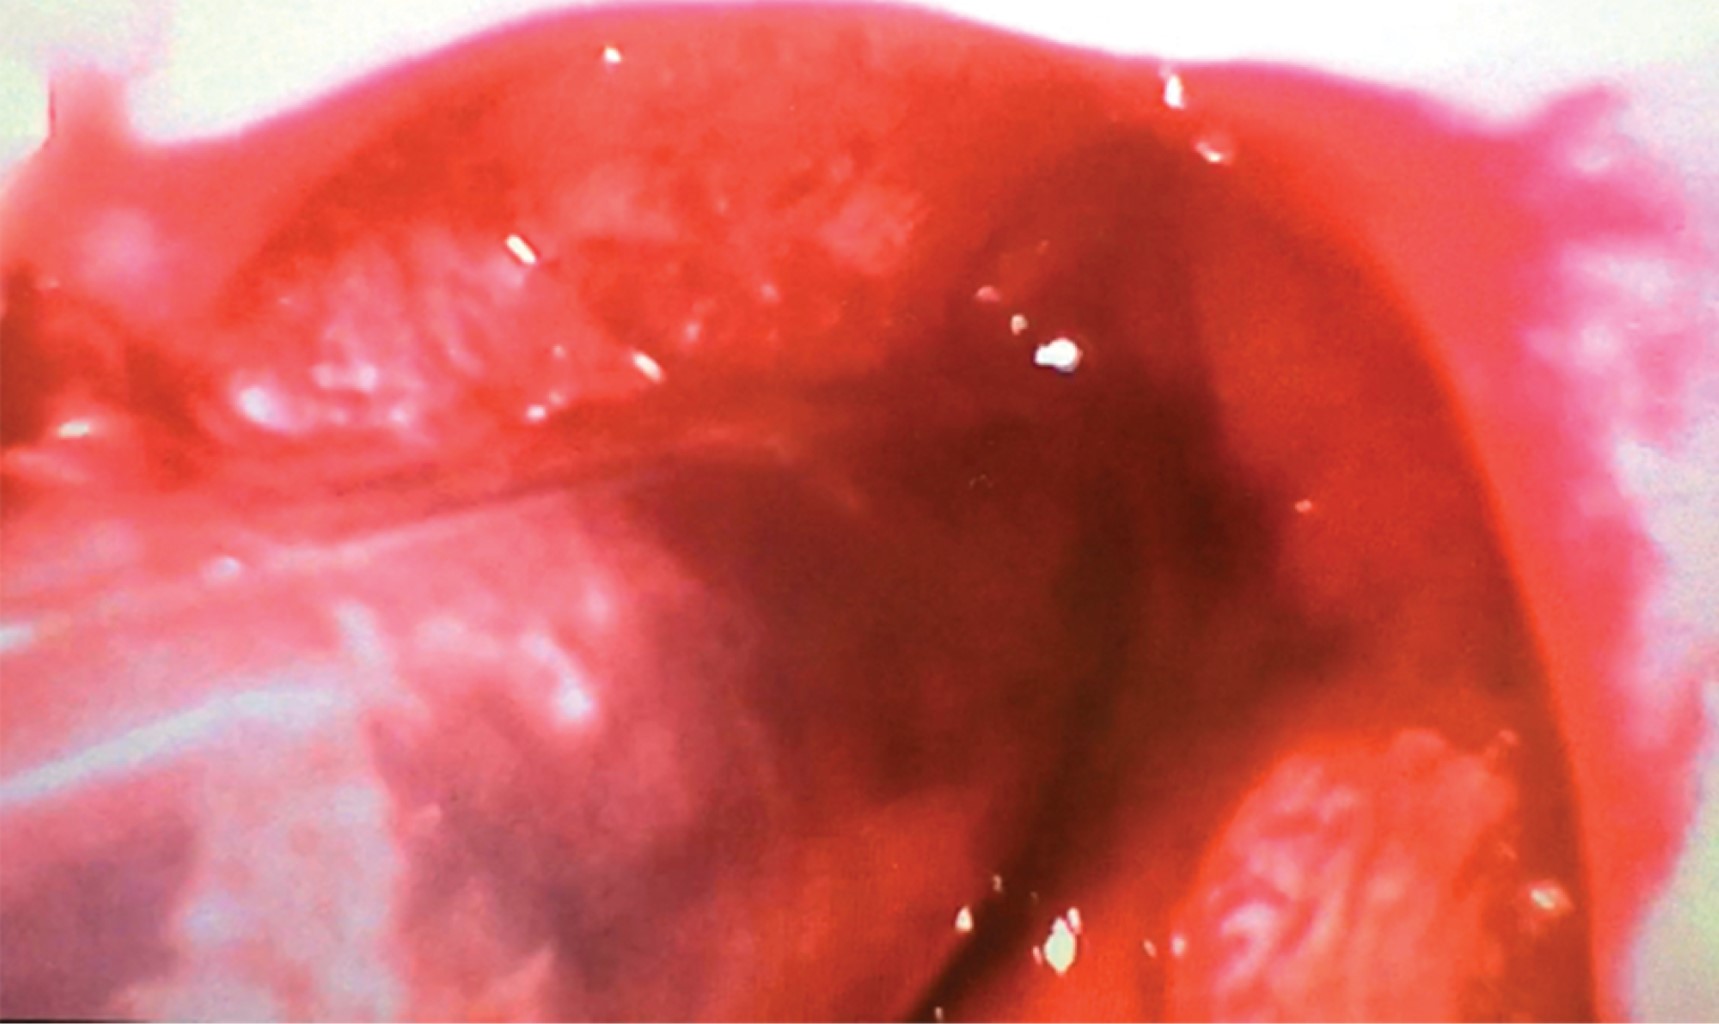

La evaluación y el manejo posterior quedaron a cargo del equipo de otorrinolaringología y cirugía de cabeza y cuello. La exploración física mostró enfisema subcutáneo, edema de región cervical y aplanamiento de la región tiroidea. Una vez el paciente ya intubado y sedado se realizó laringoscopia con sistema C-MAC-Karl Storz® observando edema de mucosa de hipofaringe, restos hemáticos, avulsión de ambas cuerdas vocales con equimosis en ventrículo laríngeo y desgarro hacia espacio paraglótico derecho (Figura 2).

Figura 2